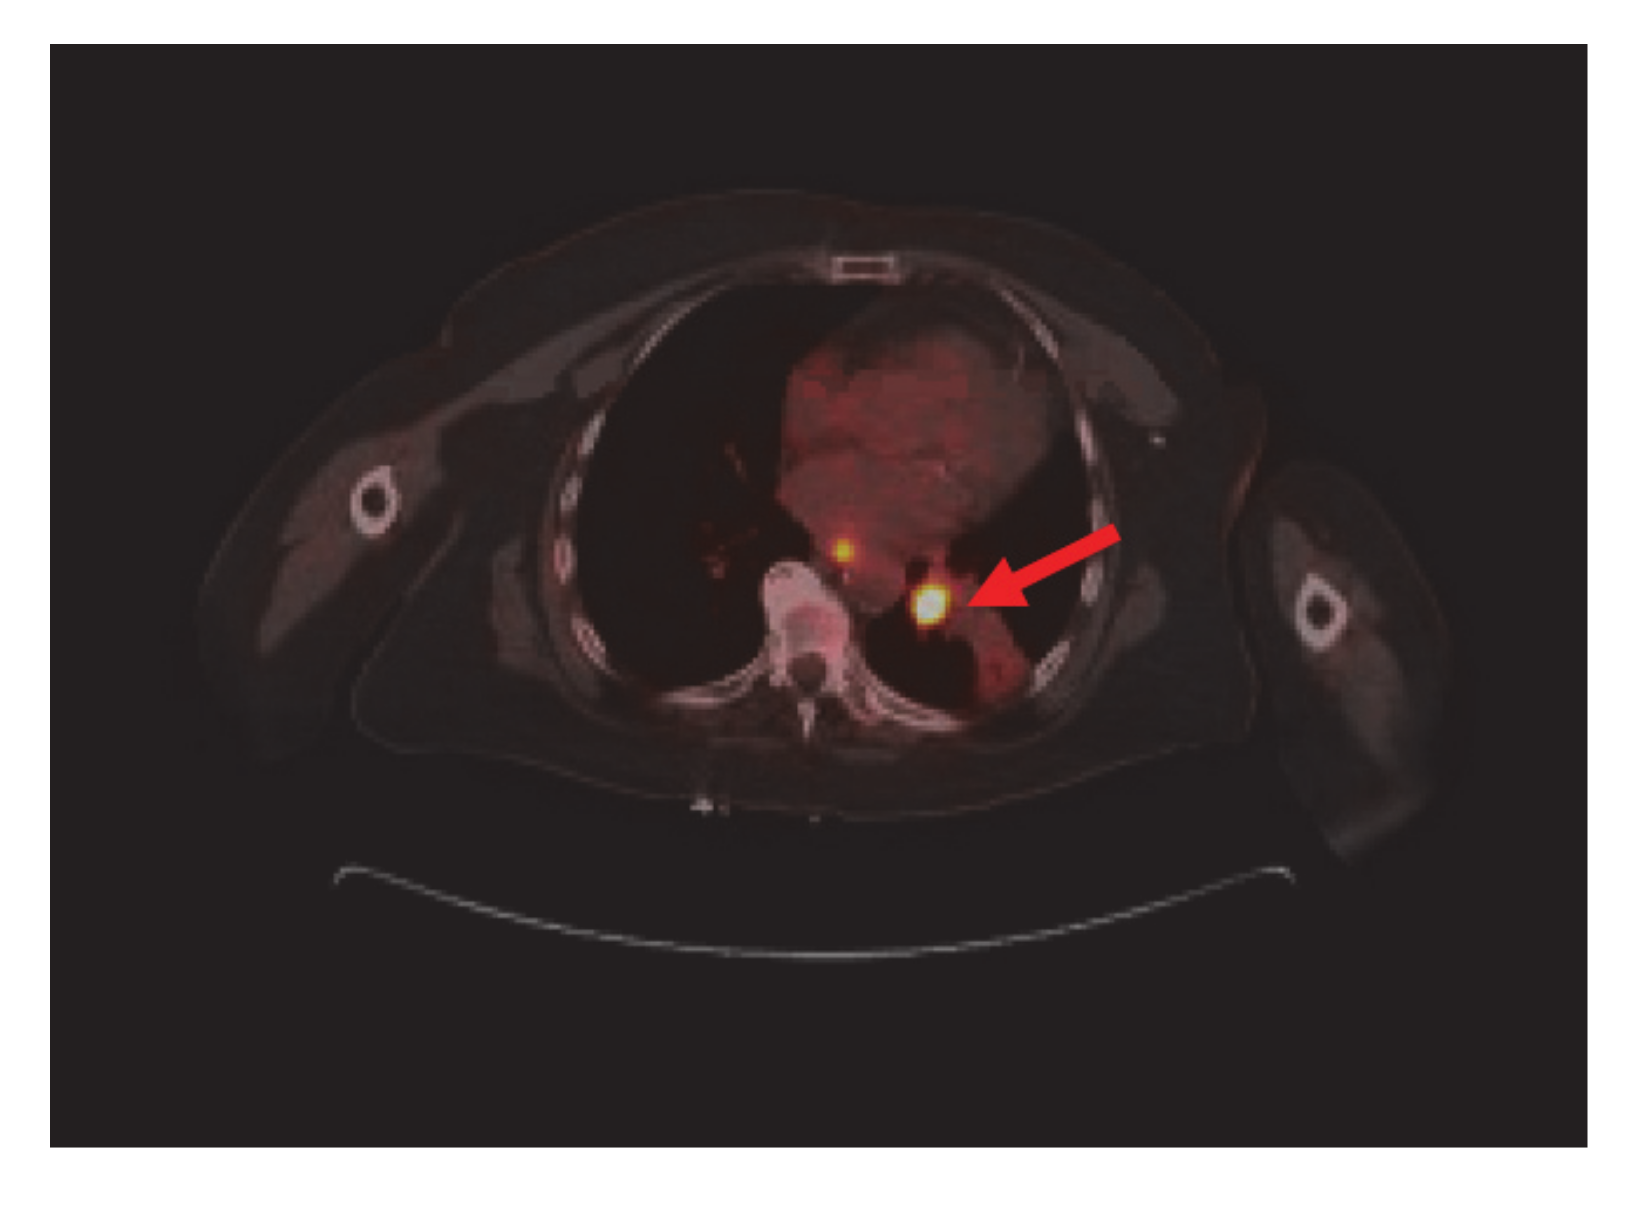

Bronchoscopy revealed endobronchial lesion involving the takeoff of the left lower lobe. PET scan showed left lower lobe hypermetabolic mass causing bronchial obstruction, distal collapse, and consolidation of basilar segments as well as subcarinal lymphadenopathy, osteolytic destruction of left acetabulum pubis, superior pubic ramus, and L3 vertebral body (Figure 2).

Figure 2.

Nuclear Medicine Positron Emission Tomography/Computer Tomography (NM PET/CT): left lower lobe hypermetabolic neoplasm (red arrow) causing bronchial obstruction and distal collapse. Metastatic mediastinal adenopathy. Not shown, L3 vertebral body, left acetabulum pubis, and superior pubic ramus metastasis.